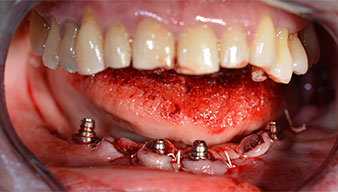

Die 64-jährige Patientin wurde mit einer Unterkiefer-Restbezahnung 38, 33 und 43 und einer klammerbefestigten Interimsprothese im Unterkiefer vorstellig (Abb. 1 und 2).

Nach der Entfernung der Unterkiefer-Restbezahnung erfolgte die krestale Schnittführung von Regio 37 bis Regio 47.

Zunächst wurde das Foramen mentale als limitierende anatomische Struktur dargestellt und die krestale Kortikalis mit dem geraden Handstück und einem großen Rosenbohrer geglättet (Abb. 4).